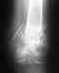

снимок 26.07.11, после которого сказали опять носить лангету так как я чувствовал легкое давление в месте перелома при движении кистью

• Кликните для загрузки файла 12. стержень 26.07.11.jpg